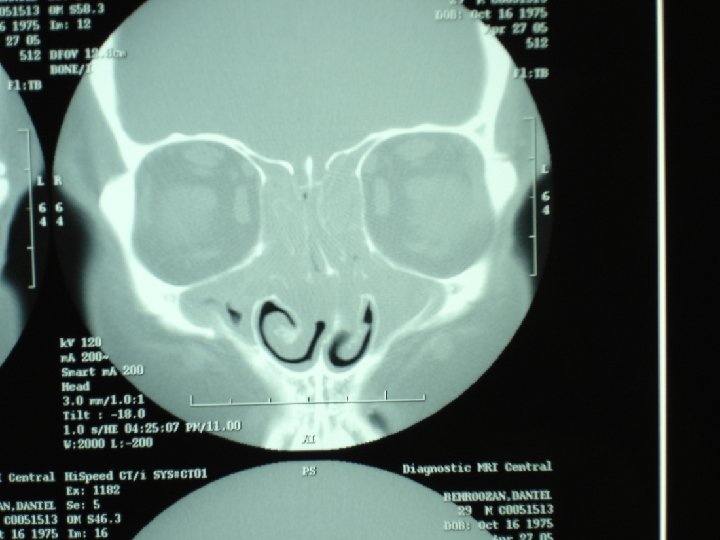

Chronic rhinosinusitis • Sinus CT scan • Consider anatomic factors— septal deviation, nasal polyps, concha bullosa, ostio-meatal blockage